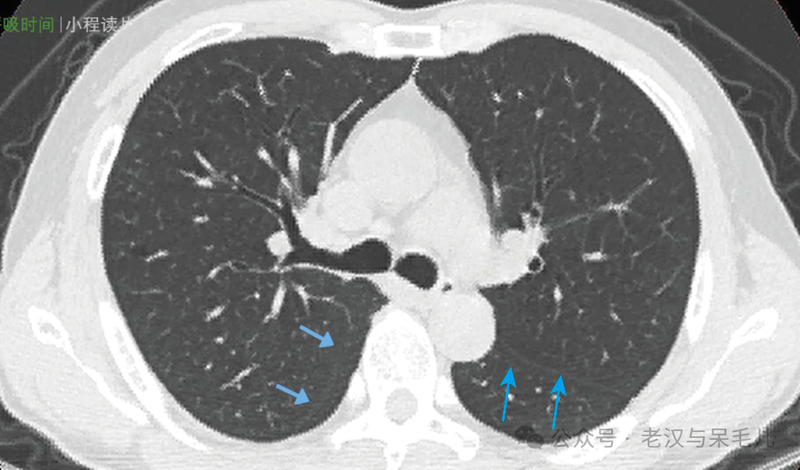

无论是左肺还是右肺,斜裂的走形都是从后上到前下,在CT横断面上表现为越靠上的斜裂越靠近后背部,越靠下的斜裂就越靠近前胸部。

左肺被斜裂分为上、下两叶,右肺被斜裂和水平裂分为上中下三叶

图片

中叶和左肺舌段水平刚好是心脏所在水平

斜裂偏上或偏下的血管纹理较少

左肺斜裂先于右肺斜裂出现,右侧斜裂出现的位置大致为气管隆突所在位置,可以粗略认为气管隆突以上均为两肺上叶